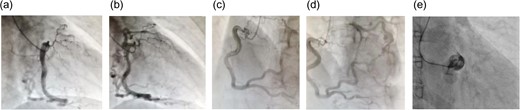

A 62-year-old woman presented with exertional chest pain. She visited our hospital because her symptoms were gradually intensifying for several years. Her only risk factor for heart disease was hypertension; she had no history of smoking, and she did not have dyslipidemia. Electrocardiography did not show any ischemic changes. On echocardiography, left ventricular function was preserved and neither hypokinesia nor valvular heart disease was observed. Further evaluation of coronary artery disease was considered necessary; therefore, she underwent a detailed examination using coronary computed tomography (CT) (Fig. 1), which revealed an LMT occlusion. Coronary angiography also revealed that the LMT was occluded at the origin. The entire left coronary artery was visualized through collateral circulation in right coronary angiography (Fig. 2). Based on blood test findings and aortic CT results, arteritis and autoimmune disease were ruled out.

Coronary angiography at the time of the initial diagnosis. (a and b) Anterior-left lateral image and (c) posterior-right lateral view. The disruption of blood flow to the LMT can be seen. Despite this disruption, the left anterior descending coronary artery and the circumflex artery demonstrate contrast enhancement. There is no indication of calcification or other lesions in the LMT.

(a and b) Right coronary angiography: right anterior oblique projection; (c and d) right coronary angiography: left anterior oblique projection; (e) left coronary angiography. During left coronary angiography, only the sinus of Valsalva is visualized, and there is no antegrade contrast enhancement in the left coronary artery. The left coronary artery is visualized through collateral pathways from the right coronary artery. The right coronary artery is more developed than the left coronary artery, and several collateral pathways can be observed.

In LMT-CTO, antegrade blood flow in the LMT is not observed with left coronary angiography. Instead, a characteristic finding is observed, in which the left coronary artery is perfused from a collateral pathway developed from the right coronary artery [3].